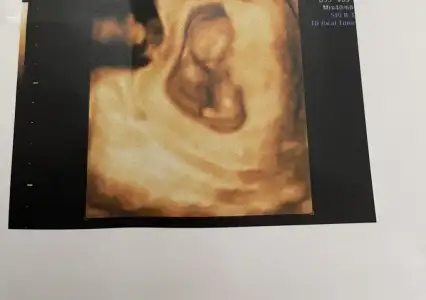

Ayy bende senin gibiyim aynı canım 13+3teyiz şuan aklım hep bebekte. Bir hareketlerini hissedebilseydikHaha mantıklı evet. Ama üç gündür iyi hissetmediğim için bebeği de merak ediyorumiçgüdüsel işte

Ayy bende senin gibiyim aynı canım 13+3teyiz şuan aklım hep bebekte. Bir hareketlerini hissedebilseydikHaha mantıklı evet. Ama üç gündür iyi hissetmediğim için bebeği de merak ediyorumiçgüdüsel işte